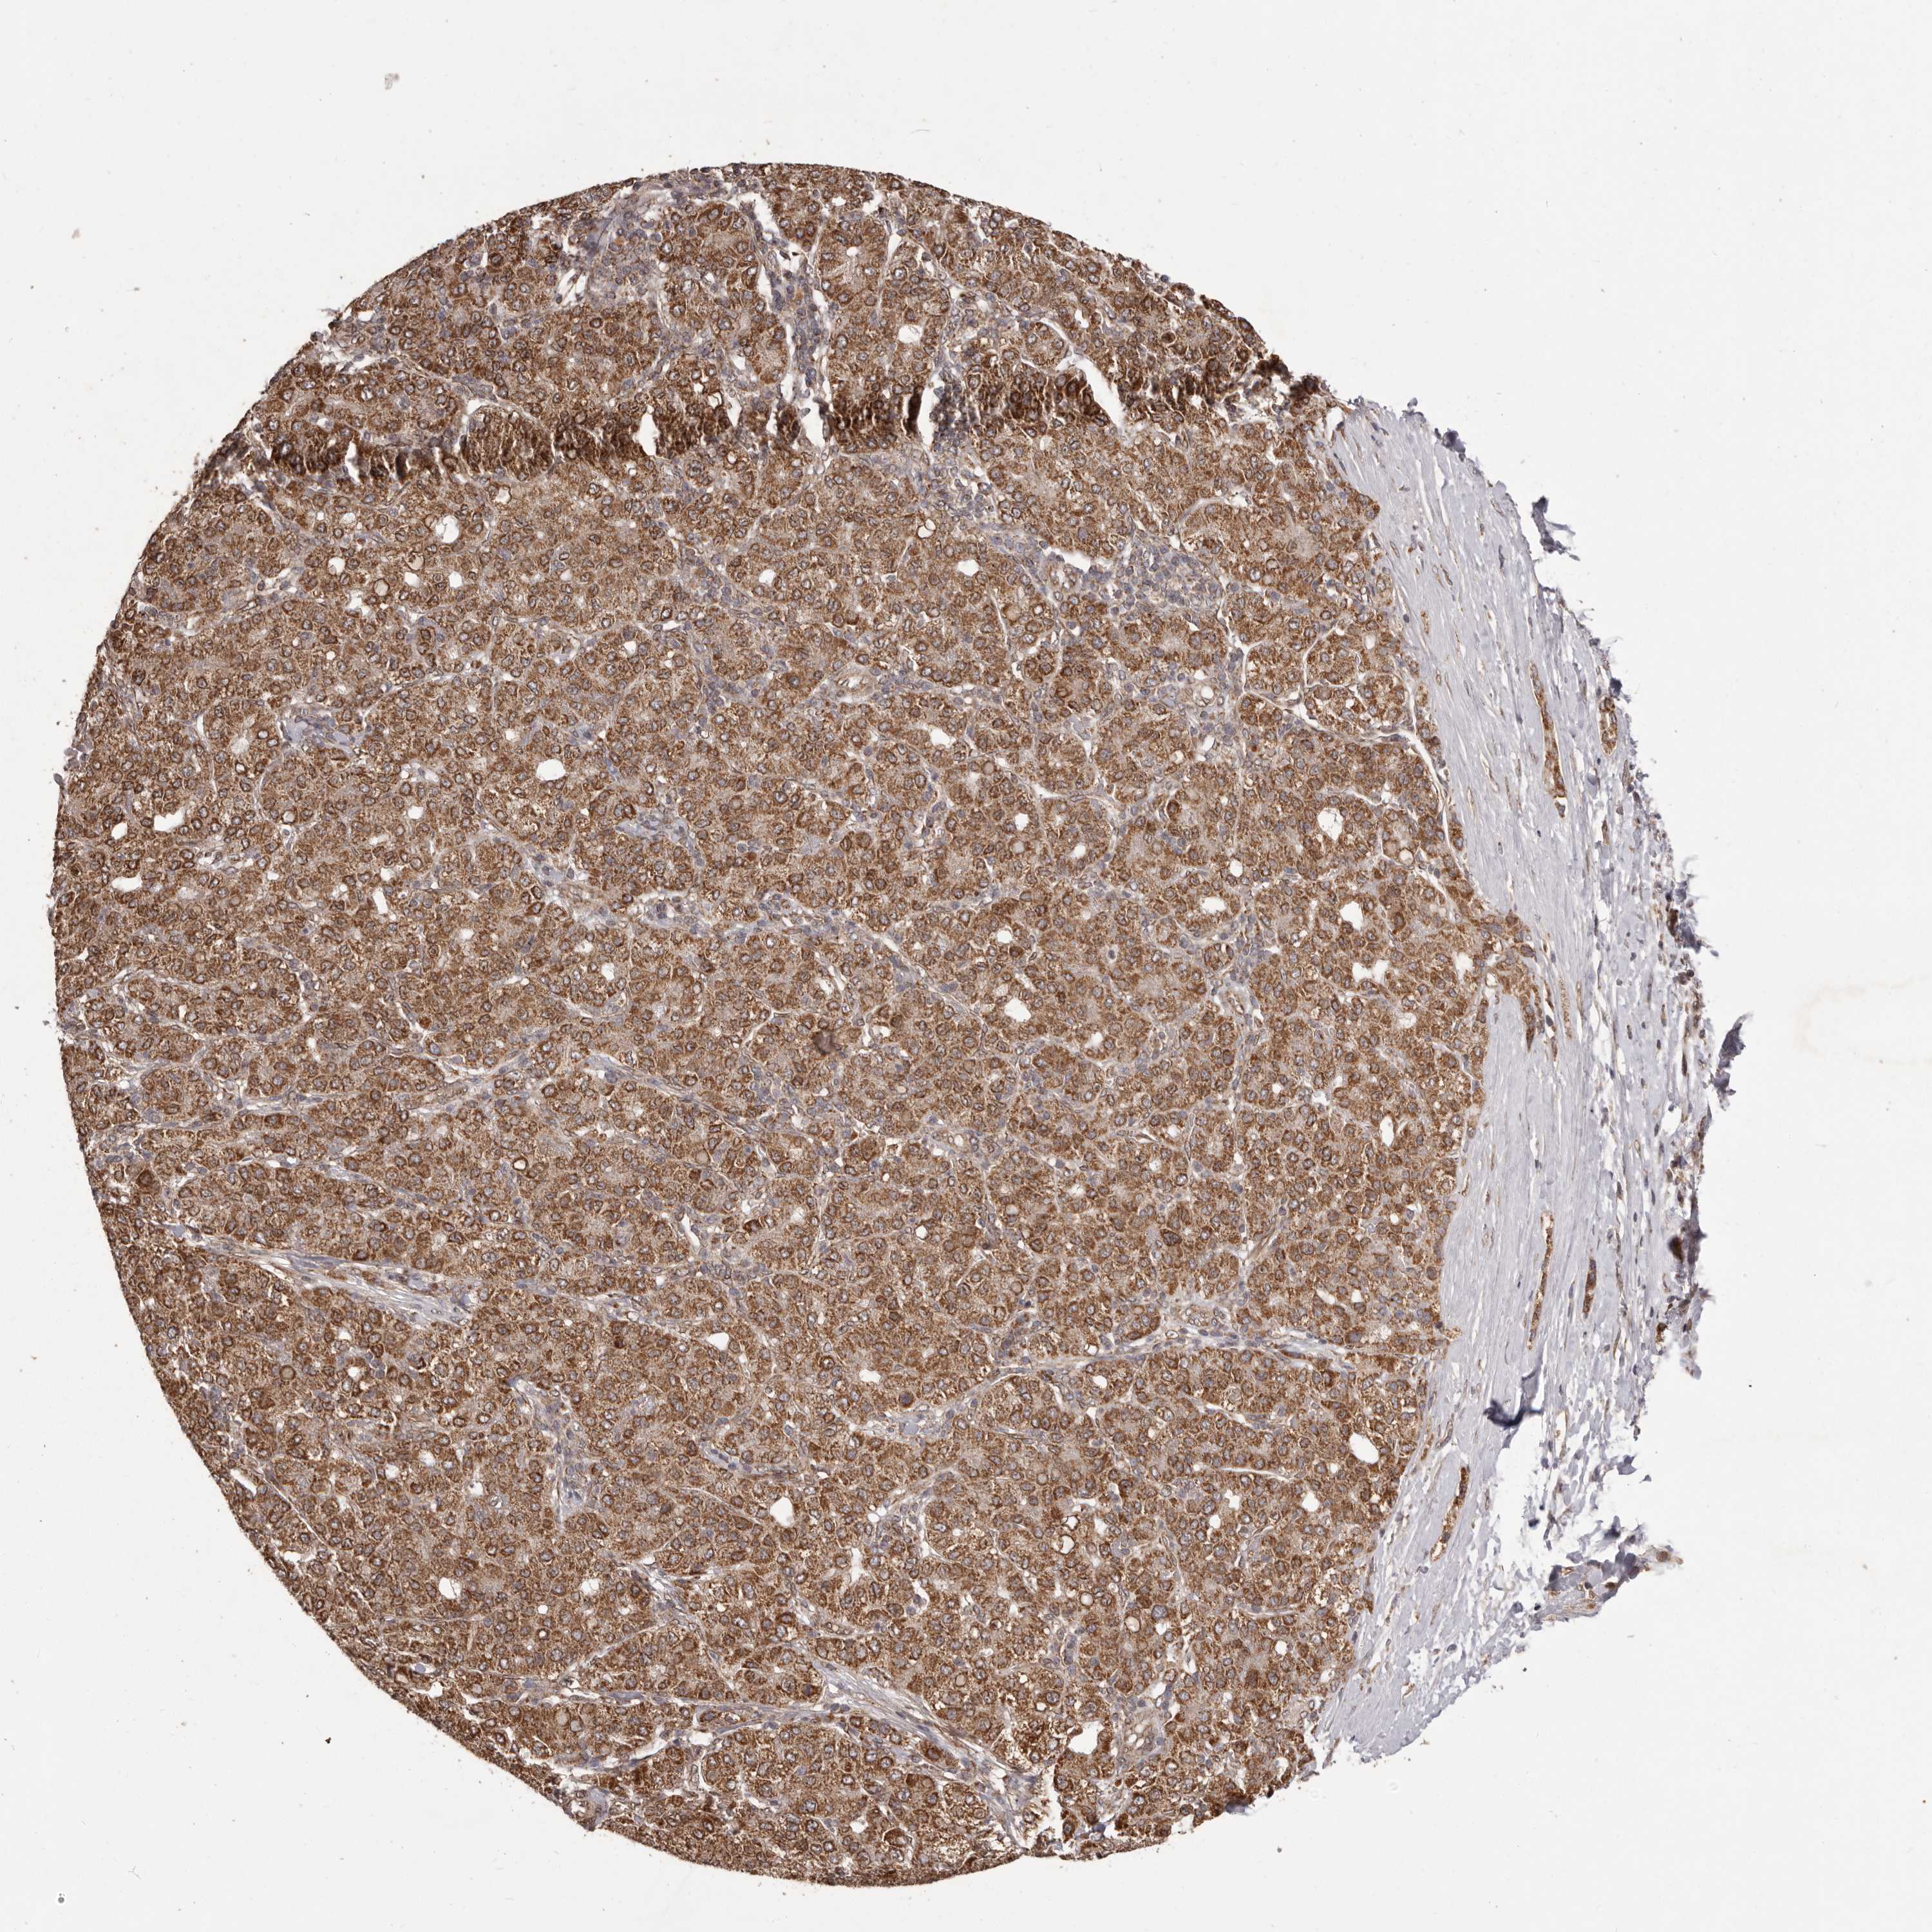

LIVER CANCER - Protein expressioni

A mouse-over function shows sample information and annotation data. Click on an image to view it in a full screen mode. Samples can be filtered based on level of antibody staining by selecting one or several of the following categories: high, medium, low and not detected. The assay and annotation is described here.

Note that samples used for immunohistochemistry by the Human Protein Atlas do not correspond to samples in the TCGA dataset.

Antibody stainingi

Antibody staining in the annotated cell types in the current human tissue is reported as not detected, low, medium, or high, based on conventional immunohistochemistry profiling in selected tissues. This score is based on the combination of the staining intensity and fraction of stained cells.

Each image is clickable and will lead to virtual microscopy that enables deeper exploration of all samples and also displays staining intensity scores, fraction scores and subcellular localization as well as patient and tissue information for each sample.

Antibody HPA029795

Antibody CAB022338

Staining

High

Medium

Low

Not detected

Intensity

Strong

Moderate

Weak

Negative

Quantity

>75%

75%-25%

<25%

None

Location

Nuclear

Cytoplasmic/membranous

Cytoplasmic/membranous,nuclear

Cholangiocarcinoma

Carcinoma, Hepatocellular, NOS